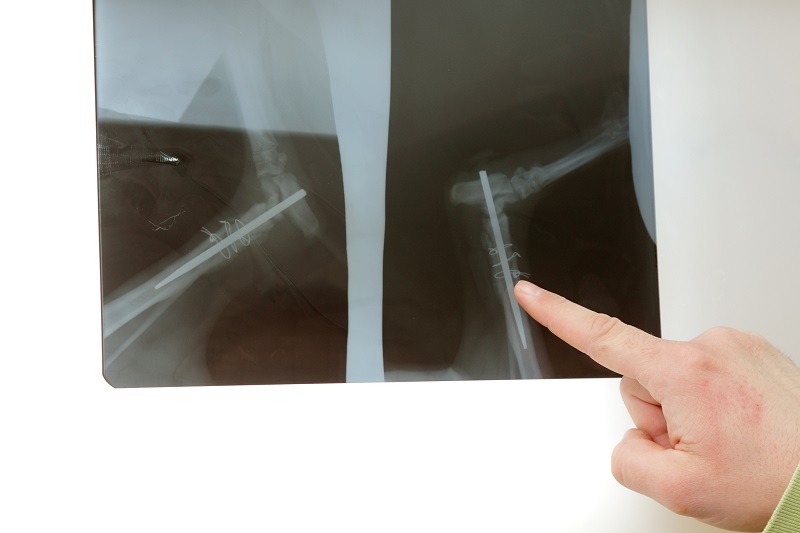

Para que os nossos pacientes beneficiem do melhor serviço possível, a Vethelp coloca ao seu dispor um aparelho de RX de alta frequência, que permite obter radiografias de qualidade em pacientes de qualquer dimensão e um Ecógrafo Doppler fixo, equipado com sondas que permitem realizar ecografias abdominais e ecocardiografias. Sendo que um exame não substitui o outro, pretendemos que ambos se completem, com o objetivo de elevar a qualidade e precisão diagnósticas.